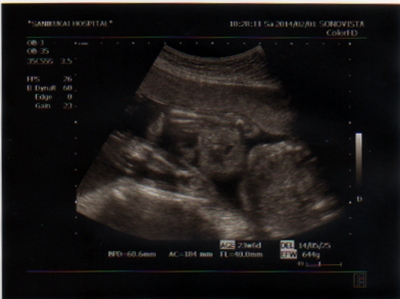

テーマ:赤ちゃん待ち 3週間ぶりの妊婦健診です! いつも通り尿検査の後に体重と血圧測定。 約4kg増です…。 おなかも大きくなってきて、これくらいは標準なのかな…と思いつつも、 あと4か月でどれだけ増加するのかと戦々恐々としております…。 土曜日ということで混み合ってはいるものの、 受付後約30分程で呼び出しが。 いつも通りエコー検査。 4日前程に4Dエコーをやったからか、白黒エコーはなんだか物足りない感じでした。 ※[注意]この下にエコー画像があります。 ...

Pretty Happy | 2014.02.02 Sun 18:00